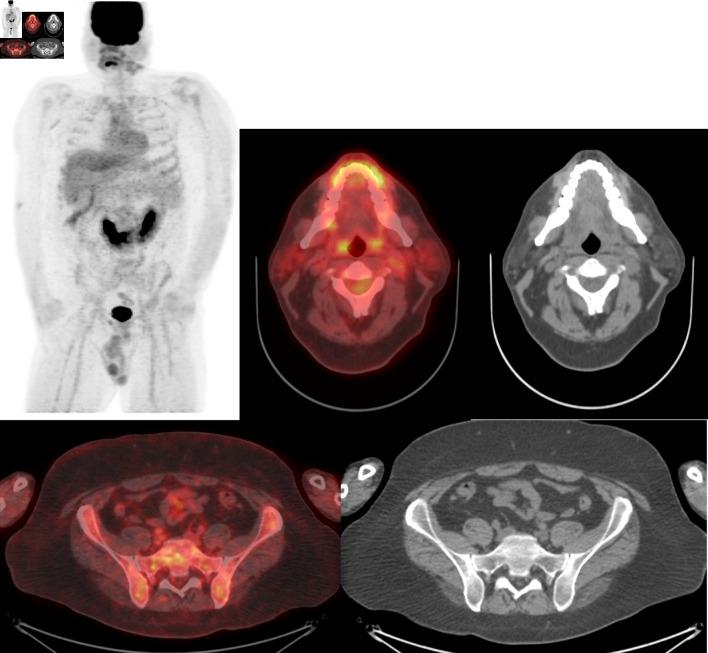

Induction multiagent chemotherapy can cure 70% of adult Burkitt lymphoma patients. However, for the remaining patients, the majority will relapse either during induction chemotherapy or within 6 months after initial complete remission, as in our patient. In this life-threatening presentation where no standard therapy exists with a response rate to salvage chemotherapy of 0% and a median survival of 6 weeks, there is an urgent need for novel, effective approaches to overcome chemoresistance in Burkitt lymphoma. Our report demonstrates that targeting B-cell receptor signaling via the phosphatidylinositol 3-kinase/protein kinase B (PI3K/AKT) pathway with copanlisib can overcome chemotherapy resistance and achieve complete remission in relapsed Burkitt lymphoma. This novel approach, followed by consolidation with allogeneic hematopoietic stem cell transplantation can provide durable complete remission by harnessing the immune graft-versus-lymphoma effect in chemoresistant Burkitt lymphoma.

诱导多药化疗可治愈70%的成年伯基特淋巴瘤患者。然而,对于其余患者,大多数会在诱导化疗期间或首次完全缓解后的6个月内复发,就像我们的患者一样。在这种危及生命的情况下,没有标准治疗方法,挽救性化疗的缓解率为0%,中位生存期为6周,迫切需要新的有效方法来克服伯基特淋巴瘤的化疗耐药性。我们的报告表明,使用库潘尼西通过磷脂酰肌醇3激酶/蛋白激酶B(PI3K/AKT)途径靶向B细胞受体信号传导,可以克服化疗耐药性,并使复发的伯基特淋巴瘤实现完全缓解。这种新方法,继之以异基因造血干细胞移植巩固治疗,可以通过利用免疫移植物抗淋巴瘤效应,在化疗耐药的伯基特淋巴瘤中实现持久的完全缓解。